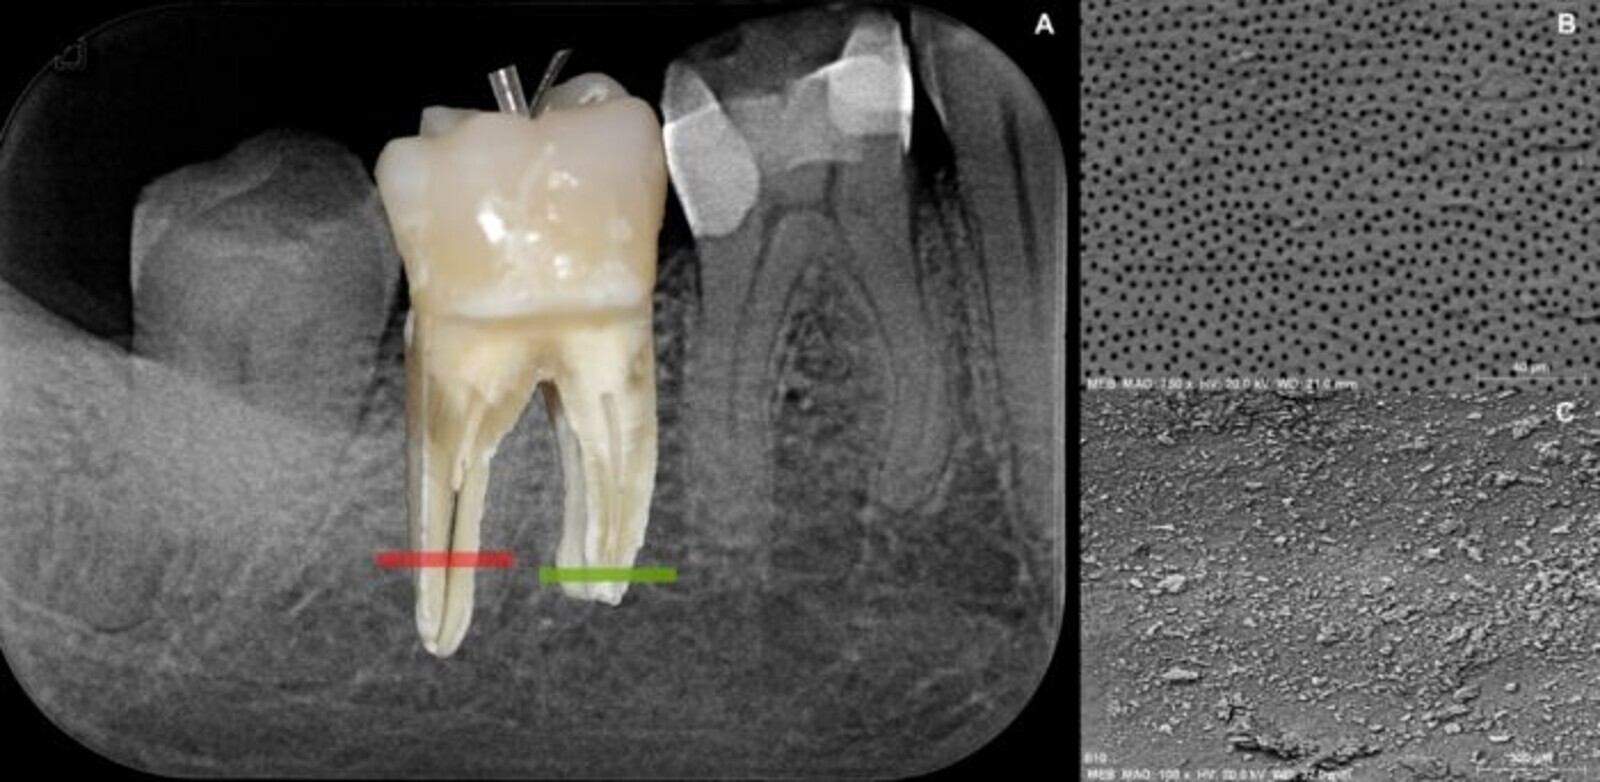

Figs. 1a–c: (a) Radiograph and superimposed photograph of a mandibular molar showing the insertion of a metallic 27-gauge Endoneedle and an IrriFlex needle. Scanning electron microscope image of (b) a clean root canal wall and a root canal wall covered with dentine slurry and pulp debris (c).

A comparative scanning electron microscope study on debris removal showed that the IrriFlex needle and syringe system was more effective than the conventional Endoneedle (Elsodent) and syringe system. The IrriFlex needle displays interesting properties during root canal irrigation. This might be explained by its flexible nature that allows it to penetrate the root canal network more easily without breaking, but also by the presence of several lateral openings at the same level, which balances the pressure and flow of the expelled irrigant. These openings ensure extra-broad exposure of the entire root canal.